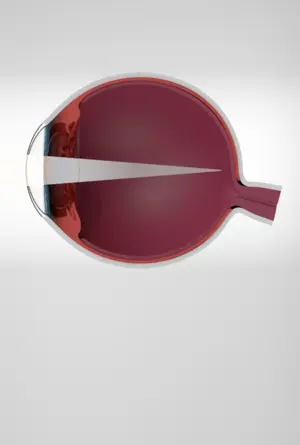

MYOPIA

When distant objects become blurry.

Myopia causes distant objects to appear blurry while close objects remain clear. It occurs when the eye focuses light in front of the retina. Common corrections include glasses, contact lenses, or laser surgery.